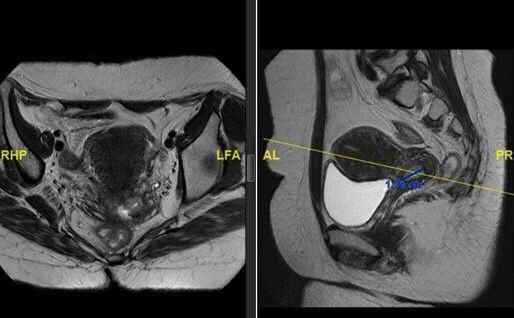

تمكن فريق طبي في مدينة الملك فهد الطبية إحدى مكونات تجمع الرياض الصحي الثاني من إدخال المعالجة الحديثة و استحداثها لأول مرة في المملكة لعلاج ورم متقدم في عنق الرحم يبلغ حجمه تقريبا 8 سم لمريضة في العقد الخامس من عمرها باستخدام التقنية الحديثة بمساعدة العلاج الإشعاعي التداخلي المعقد انترستيشيل

وأوضح رئيس الفريق المتخصص في العلاج الإشعاعي التداخلي المعقد الاستشاري سعد الرشيدي أن هذه التقنية تستخدم لمعالجة أغلب أورام النساء المعقدة وخاصة عند رجوعها في الحوض بما فيها الأورام المتقدمة جدا حيث يتم زرع القسطرة داخل الورم لإيصال جرعات إشعاعية عالية للقضاء على الورم والتي لا تتم بالطريقة التقليدية.

وأضاف د. الرشيدي أن هذه التقنية تحتاج إلى تدريب عالي الدقة ولا توجد حاليا إلا في دول شمال أمريكا و أوروبا وتحتاج المعالجة بهذه التقنية إلى مركز متكامل ومتخصص بهذا العلاج حيث يتم تقييم المريض في العيادة ومن ثم عمل الفحوصات الأشعات التي تتضمن الرنين المغناطيسي ويبدأ المريض في العلاج الإشعاعي الخارجي والكيماوي لعدة جلسات تتبعها هذه التقنية الحديثة.